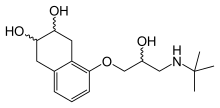

Propanolamines are a class of chemical compounds, many of which are pharmaceutical drugs. They are amino alcohols that are derivatives of 1-amino-2-propanol.[1]

Propanolamines include: